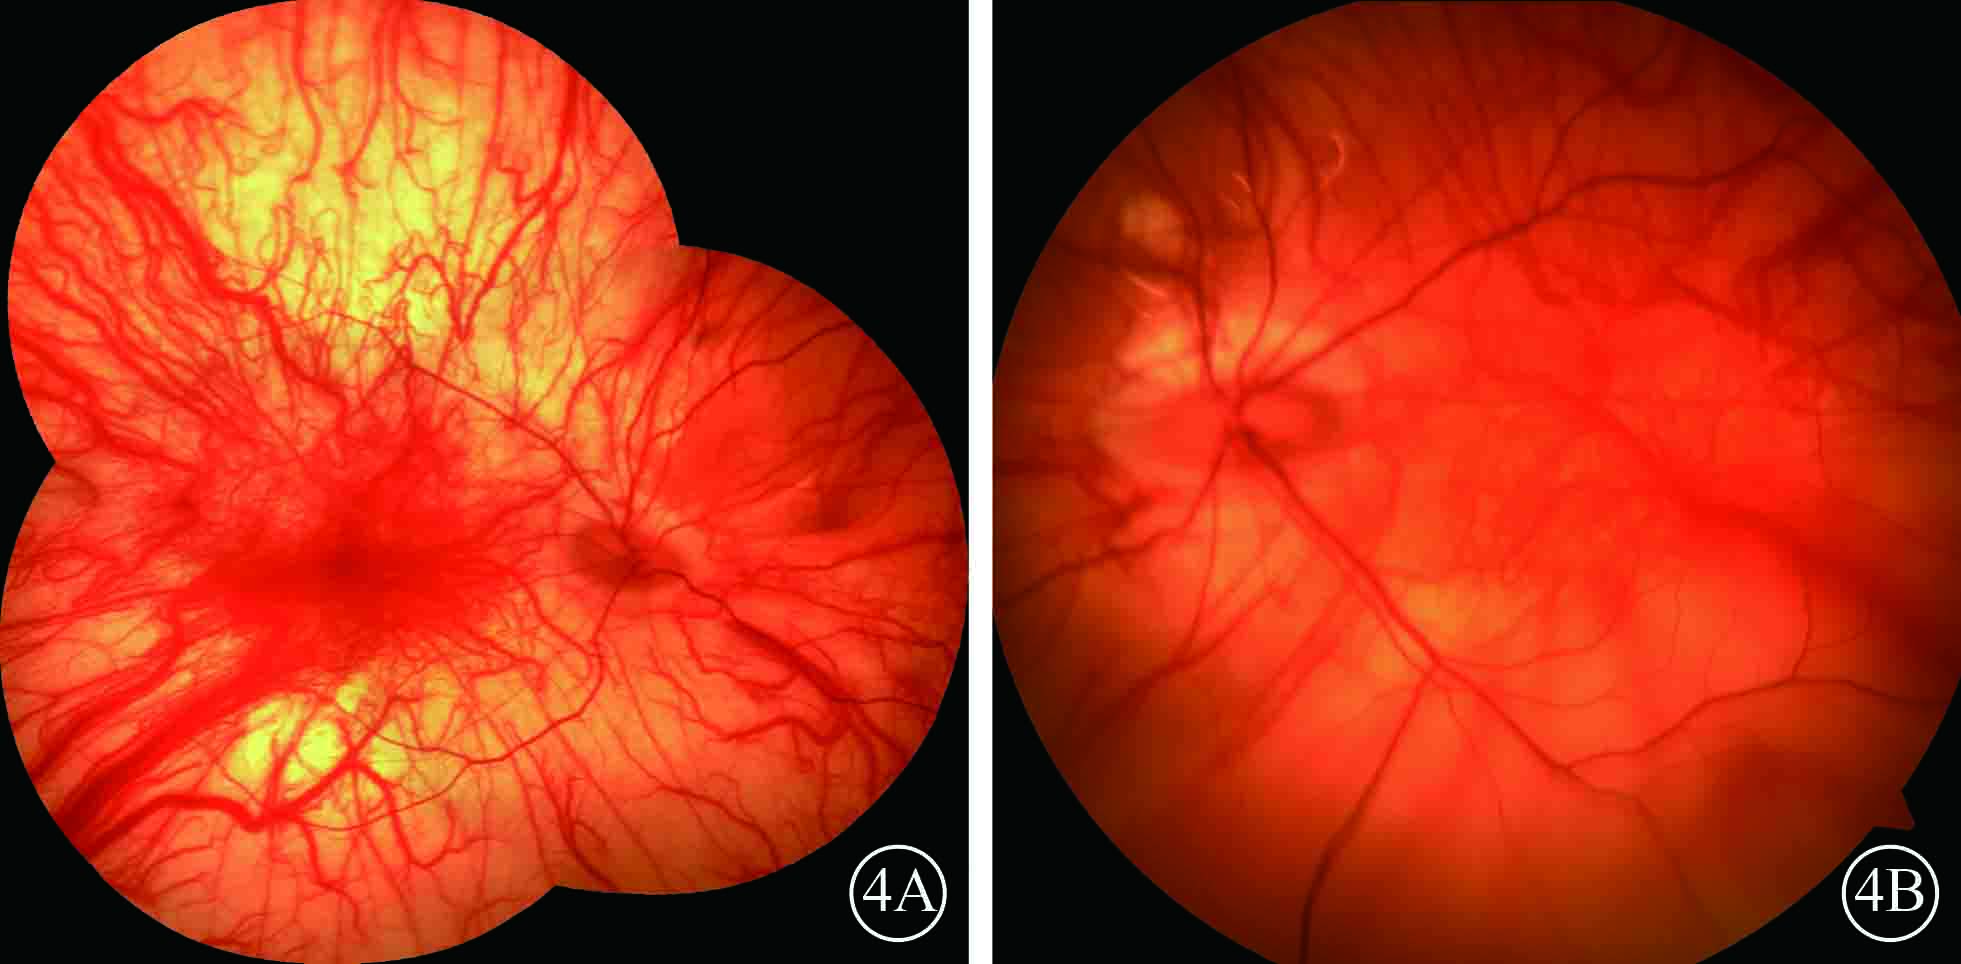

患者男,35歲。因體檢發現雙眼視網膜脫離1月余于2015年3月12日來我院眼科就診。患者自幼皮膚、毛發、虹膜無色素;雙眼視力差、畏光。否認外傷史、家族史。眼部檢查:右眼視力數指/30 cm,左眼視力0.1;雙眼矯正視力均無提高。雙眼眼瞼皮膚及睫毛均無色素;眼球水平震顫;角膜透明,瞳孔圓,虹膜半透明;晶狀體透明。雙眼眼底呈橙色。右眼全視網膜脫離,左眼0~8點時鐘位視網膜脫離(圖1);雙眼視網膜裂孔均窺不清。A型超聲檢查,右眼、左眼眼軸長度分別為26、28 mm。診斷:(1)雙眼孔源性視網膜脫離(疑似);(2)雙眼高度近視;(3)眼皮膚白化病。分別于2015年3月23日、5月11日行左眼、右眼視網膜復位手術。采用標準25G經睫狀體平坦部玻璃體切割手術。手術中見左眼視網膜裂孔分別位于 1、2、4、6點時鐘位,右眼裂孔位于8、11點時鐘位。先采用眼內電凝對裂孔邊緣進行標記,電凝處理后裂孔邊緣呈白色外觀(圖2);視網膜復位后,采用視網膜冷凍替代常規激光光凝對裂孔進行封閉;最后進行硅油眼內填充。雙眼均于手術后3個月行硅油取出手術。硅油取出后3個月,雙眼視網膜復位良好,眼底呈橙色,透見脈絡膜大血管(圖3);6個月,右眼視網膜復位良好,左眼下方視網膜再次脫離。于2016年2月1日再次行左眼視網膜復位手術、硅油填充。2016年12月27日隨訪,右眼視網膜復位良好;左眼硅油填充,下方視網膜仍有局部脫離(圖4)。

末次隨訪雙眼彩色眼底像。4A. 右眼,視網膜復位良好;4B. 左眼,下方視網膜脫離

末次隨訪雙眼彩色眼底像。4A. 右眼,視網膜復位良好;4B. 左眼,下方視網膜脫離

患者男,35歲。因體檢發現雙眼視網膜脫離1月余于2015年3月12日來我院眼科就診。患者自幼皮膚、毛發、虹膜無色素;雙眼視力差、畏光。否認外傷史、家族史。眼部檢查:右眼視力數指/30 cm,左眼視力0.1;雙眼矯正視力均無提高。雙眼眼瞼皮膚及睫毛均無色素;眼球水平震顫;角膜透明,瞳孔圓,虹膜半透明;晶狀體透明。雙眼眼底呈橙色。右眼全視網膜脫離,左眼0~8點時鐘位視網膜脫離(圖1);雙眼視網膜裂孔均窺不清。A型超聲檢查,右眼、左眼眼軸長度分別為26、28 mm。診斷:(1)雙眼孔源性視網膜脫離(疑似);(2)雙眼高度近視;(3)眼皮膚白化病。分別于2015年3月23日、5月11日行左眼、右眼視網膜復位手術。采用標準25G經睫狀體平坦部玻璃體切割手術。手術中見左眼視網膜裂孔分別位于 1、2、4、6點時鐘位,右眼裂孔位于8、11點時鐘位。先采用眼內電凝對裂孔邊緣進行標記,電凝處理后裂孔邊緣呈白色外觀(圖2);視網膜復位后,采用視網膜冷凍替代常規激光光凝對裂孔進行封閉;最后進行硅油眼內填充。雙眼均于手術后3個月行硅油取出手術。硅油取出后3個月,雙眼視網膜復位良好,眼底呈橙色,透見脈絡膜大血管(圖3);6個月,右眼視網膜復位良好,左眼下方視網膜再次脫離。于2016年2月1日再次行左眼視網膜復位手術、硅油填充。2016年12月27日隨訪,右眼視網膜復位良好;左眼硅油填充,下方視網膜仍有局部脫離(圖4)。

末次隨訪雙眼彩色眼底像。4A. 右眼,視網膜復位良好;4B. 左眼,下方視網膜脫離

末次隨訪雙眼彩色眼底像。4A. 右眼,視網膜復位良好;4B. 左眼,下方視網膜脫離